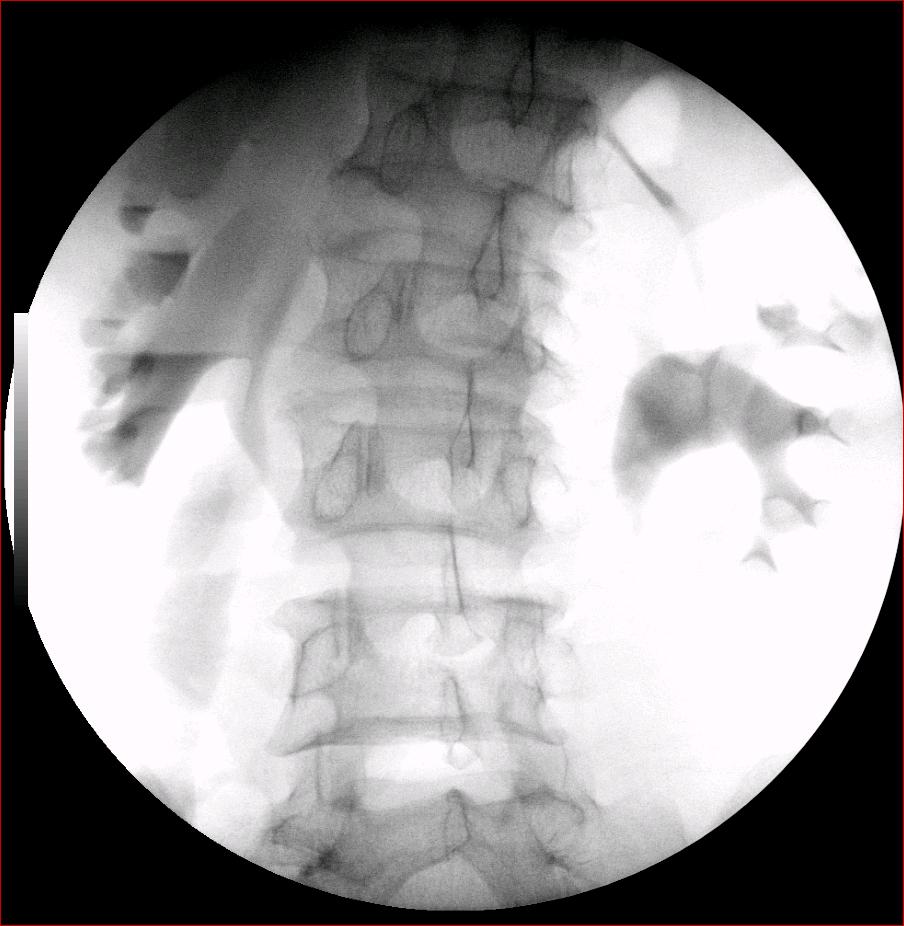

以下是引用luoxinjun在2008-2-18 15:54:00的发言:[br]右肾积水,右输尿管下端结石

以下是引用zhangxiangjun在2008-2-18 21:01:00的发言:[br]右输尿管盆段末端结石,继发其近端输尿管、右肾积水。

以下是引用hexue在2008-2-18 17:33:00的发言:[br]右输尿管下段结石并右肾及右输尿管积水扩张

以下是引用杀毒软件在2008-2-18 16:24:00的发言:[br]右输尿管下段结石,肾盂积水。